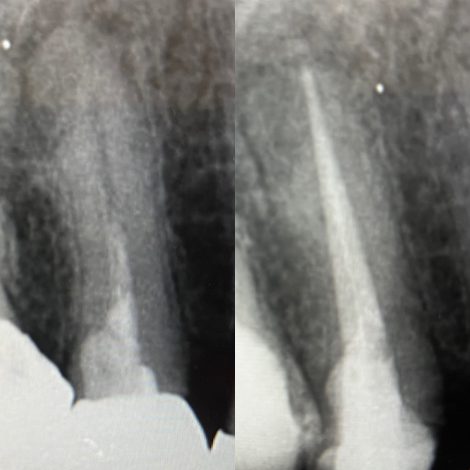

今日ご紹介する症例は 他院で治療セラミック修復を行い、その後、根の中が感染を起こしてしまったケースです🦷 抜歯の選択も提案されたそうですが、保存を希望され当院受診されました 確かに抜歯してイン…